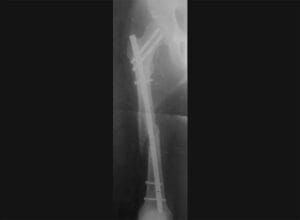

Po nehode na lyžiach v 2009 som pol roka nemohol chodiť bez pomoci barlí a venoval som sa hlavne rekonvalescencii a rehabilitácii. Lekár mi hovoril, že na šport môžem zabudnúť. Nič iné v tom momente nebolo podstatné, iba túžba vrátiť sa naspäť do normálneho života. Mal som pocit, že sa môj život neuberá, tak ako by som chcel.